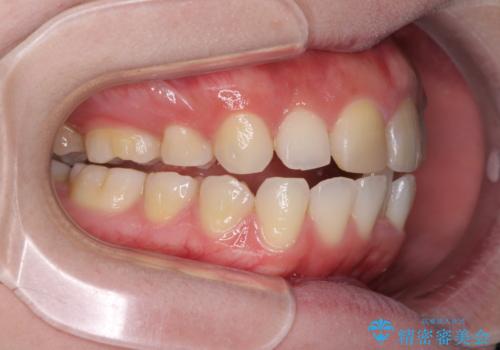

抜歯矯正の後戻り インビザラインによるオープンバイトの再矯正

- 以前矯正治療をされていましたが、後戻りが起きたことを気にして来院された患者様です。

上下前歯のオープンバイトを改善するため、インビザラインにて治療を行うこととしました。

外食が楽しみである患者様だったので、インビザラインによる治療期間は我慢の時期であったようです。

自己管理を徹底していただいたので、1年程度で治療を終えることができました。